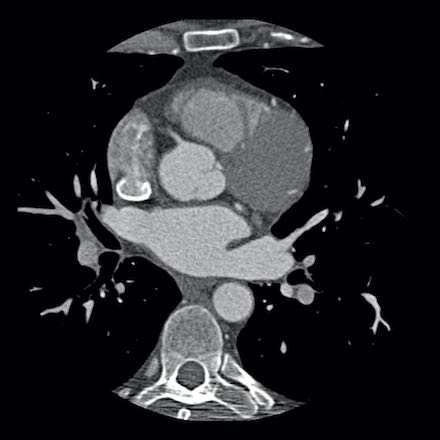

case 1 – CAD-RADS 2/P1

First, scroll through the scan.

Not all images are included. Some images without any abnormalities are skipped

from the series.

How would you describe the findings on the coronary CTA?

The findings are:

- Agatston score of

this patient was 14 (P1). Please, also note the calcification of the aortic valve. - Some partially

calcified and calcified plaques are present in the LAD with mild stenosis

(25-49%). - Calcified-plaque in

the LCX causing minimal stenosis (<25%). - Non-calcified

plaque in the distal RCA causing minimal stenosis (<25%). - This patient classifies

as CAD-RADS 2/P1, which means no further workup is needed.